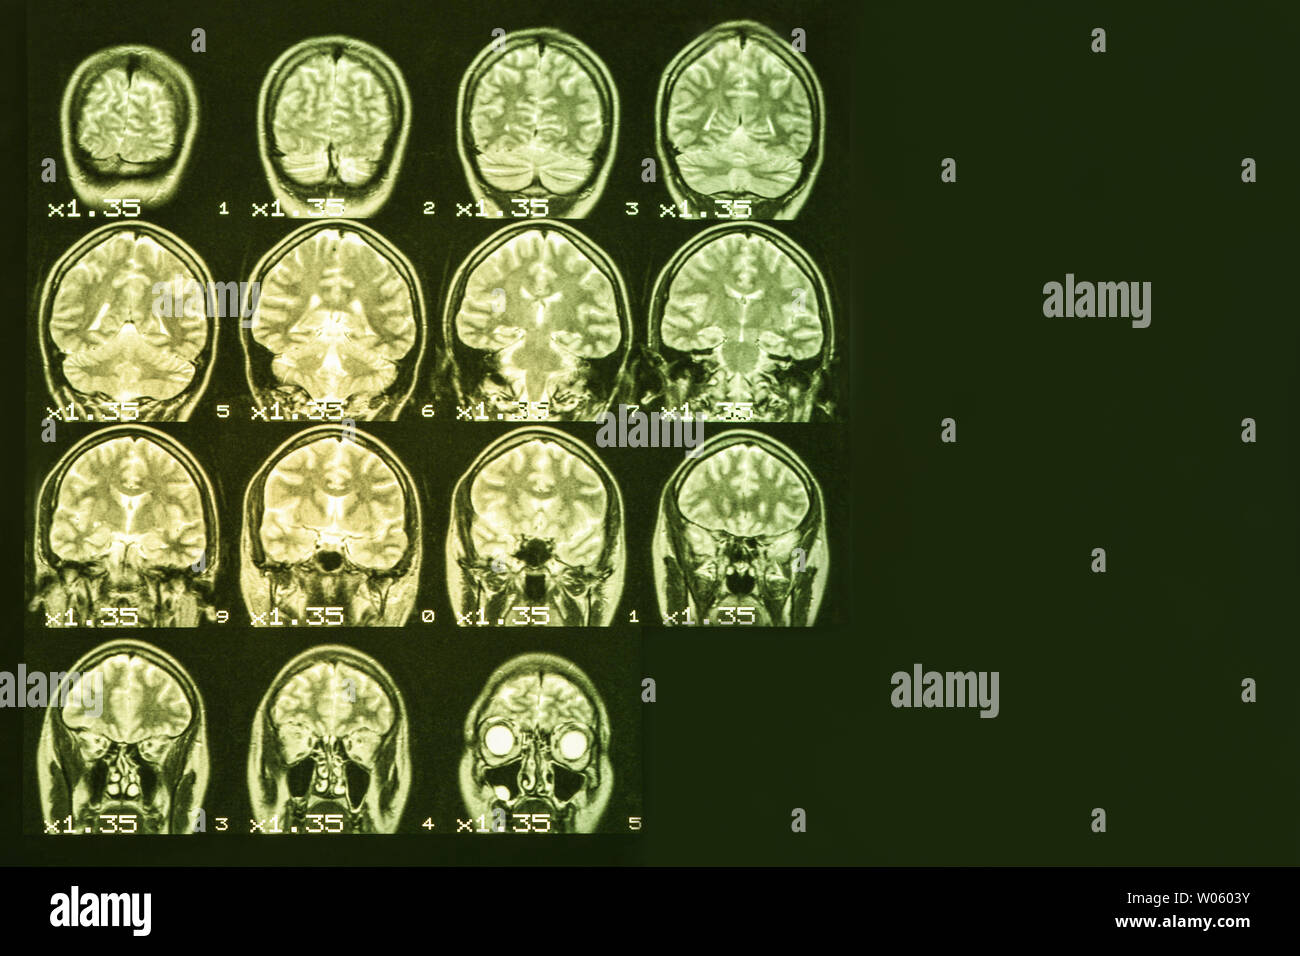

MRI magnetic resonance image scan of a patient with a tumor in the brain stem. Stock Photohttps://www.alamy.com/image-license-details/?v=1https://www.alamy.com/mri-magnetic-resonance-image-scan-of-a-patient-with-a-tumor-in-the-brain-stem-image236792137.html

MRI magnetic resonance image scan of a patient with a tumor in the brain stem. Stock Photohttps://www.alamy.com/image-license-details/?v=1https://www.alamy.com/mri-magnetic-resonance-image-scan-of-a-patient-with-a-tumor-in-the-brain-stem-image236792137.htmlRFRN6PP1–MRI magnetic resonance image scan of a patient with a tumor in the brain stem.

MRI Brain Scan of head and skull Stock Photohttps://www.alamy.com/image-license-details/?v=1https://www.alamy.com/mri-brain-scan-of-head-and-skull-image244052359.html

MRI Brain Scan of head and skull Stock Photohttps://www.alamy.com/image-license-details/?v=1https://www.alamy.com/mri-brain-scan-of-head-and-skull-image244052359.htmlRFT51F7K–MRI Brain Scan of head and skull